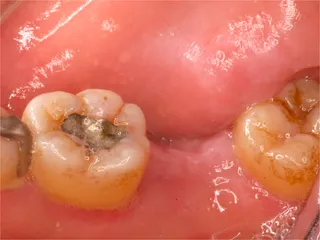

| 保険ブリッジ |

保険ブリッジ・頬側

■長所 ・安い ■短所 ・前後の歯を削り犠牲にする ※前後の歯を削り被せものをします ※抜けた歯のかわりに金属が付いています |